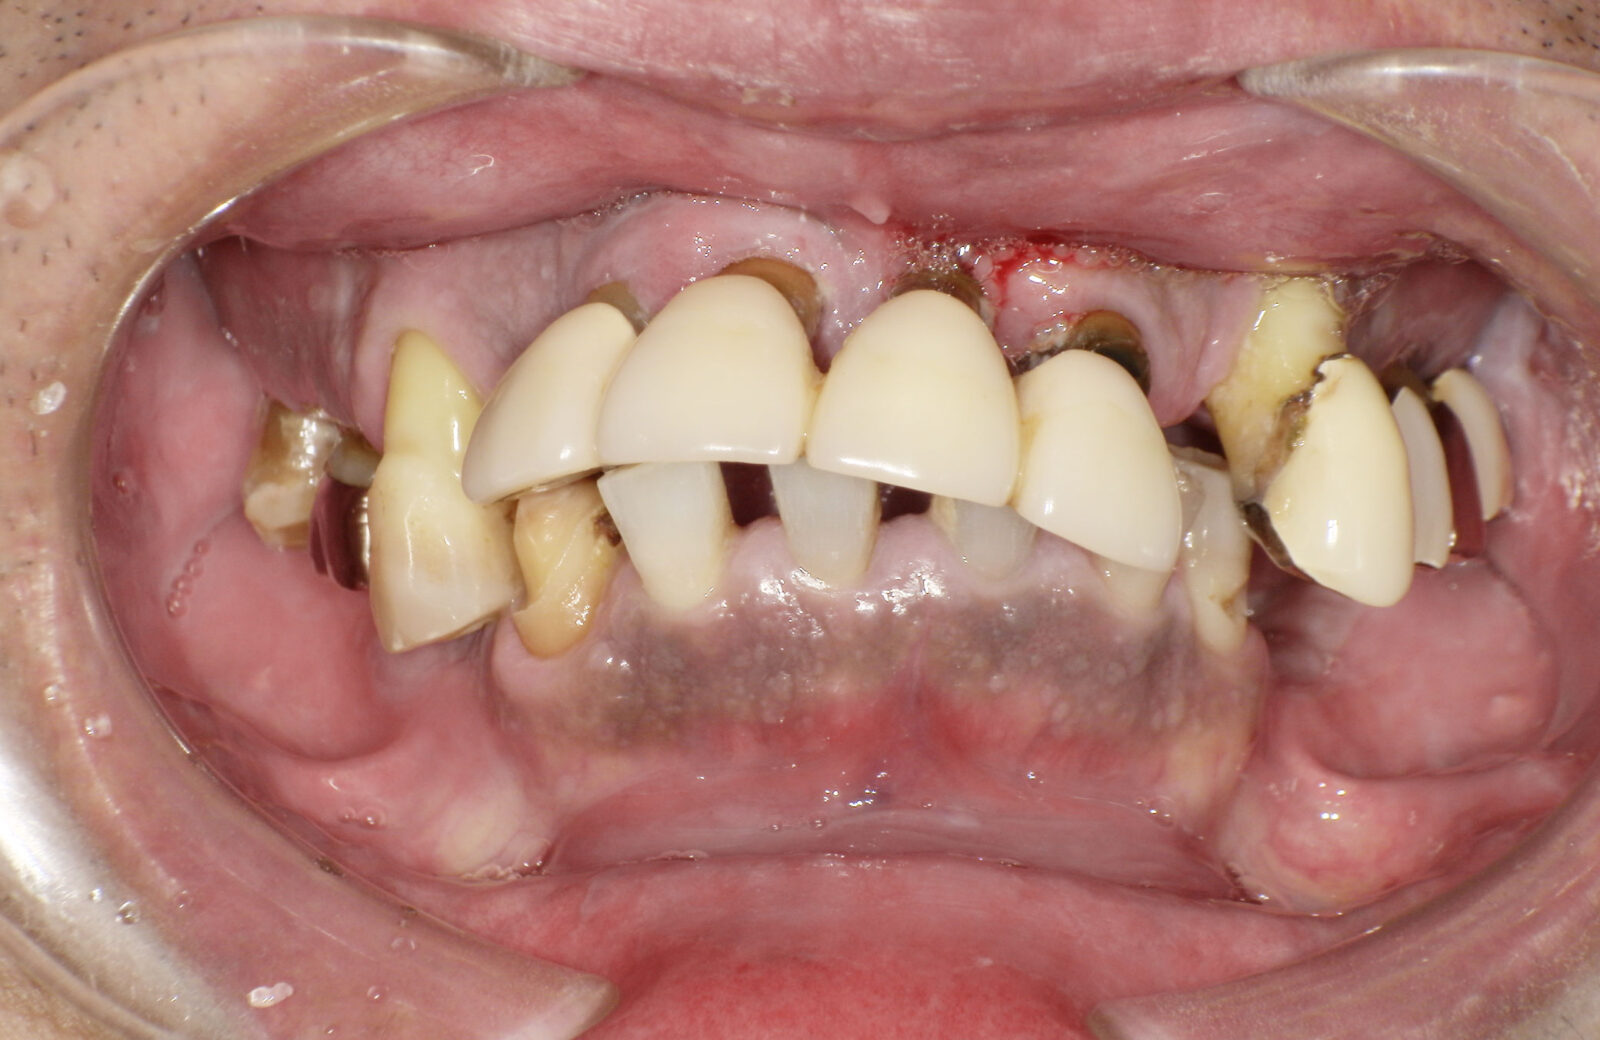

• 治療前

ボロボロの歯を「総合歯科治療」で ※保険外※

ボロボロの状態の治療は「包括的かつ総合的な治療」が必要となります。そのため当院では保険外で治療を行います。

多くの方が、重度のむし歯や歯周病で、抜けてしまっている歯もあるため、まずは虫歯や歯周病治療を行い、残せる歯はしっかり残したうえで、欠損部分の治療を行います。欠損部分に関しては、インプラント、ブリッジ、入れ歯、ケースによってはオールオン4という治療の中から治療法を決定します。